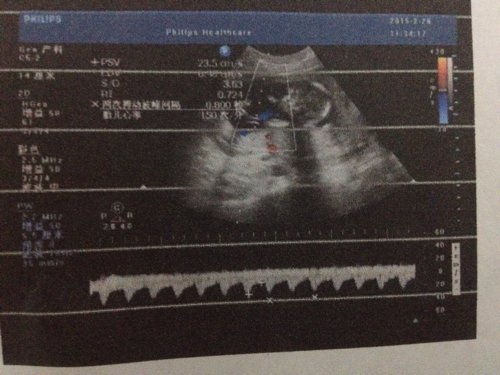

请各路神医帮我分析(1)这三张分别是哪些部位的彩超图?(2)胎儿性别?(3)胎儿是否健康? 请各路神医帮我分析。(1)这三张分别是哪些部位的彩超图?(2)胎儿性别?(3)胎儿是否健康?有无任何畸形或病变?(4)子宫和羊水是否完好?(5)胎儿有多大?(6)肾脏是否有何病变? 点击展开 匿名用户 2015-02-28 12:03 为您推荐: 其他回答 性别看不出来,这个时候了,性别很重要吗?健康是最重要的。 孩子没事啊,有事的话,医生会跟你说的。想太多了 安心养胎吧 匿名用户 2015-02-28 16:37 相关问题 22W四维彩超结果帮我看看胎儿性别 四维彩超怎样看胎儿性别 四维彩超能看胎儿性别吗